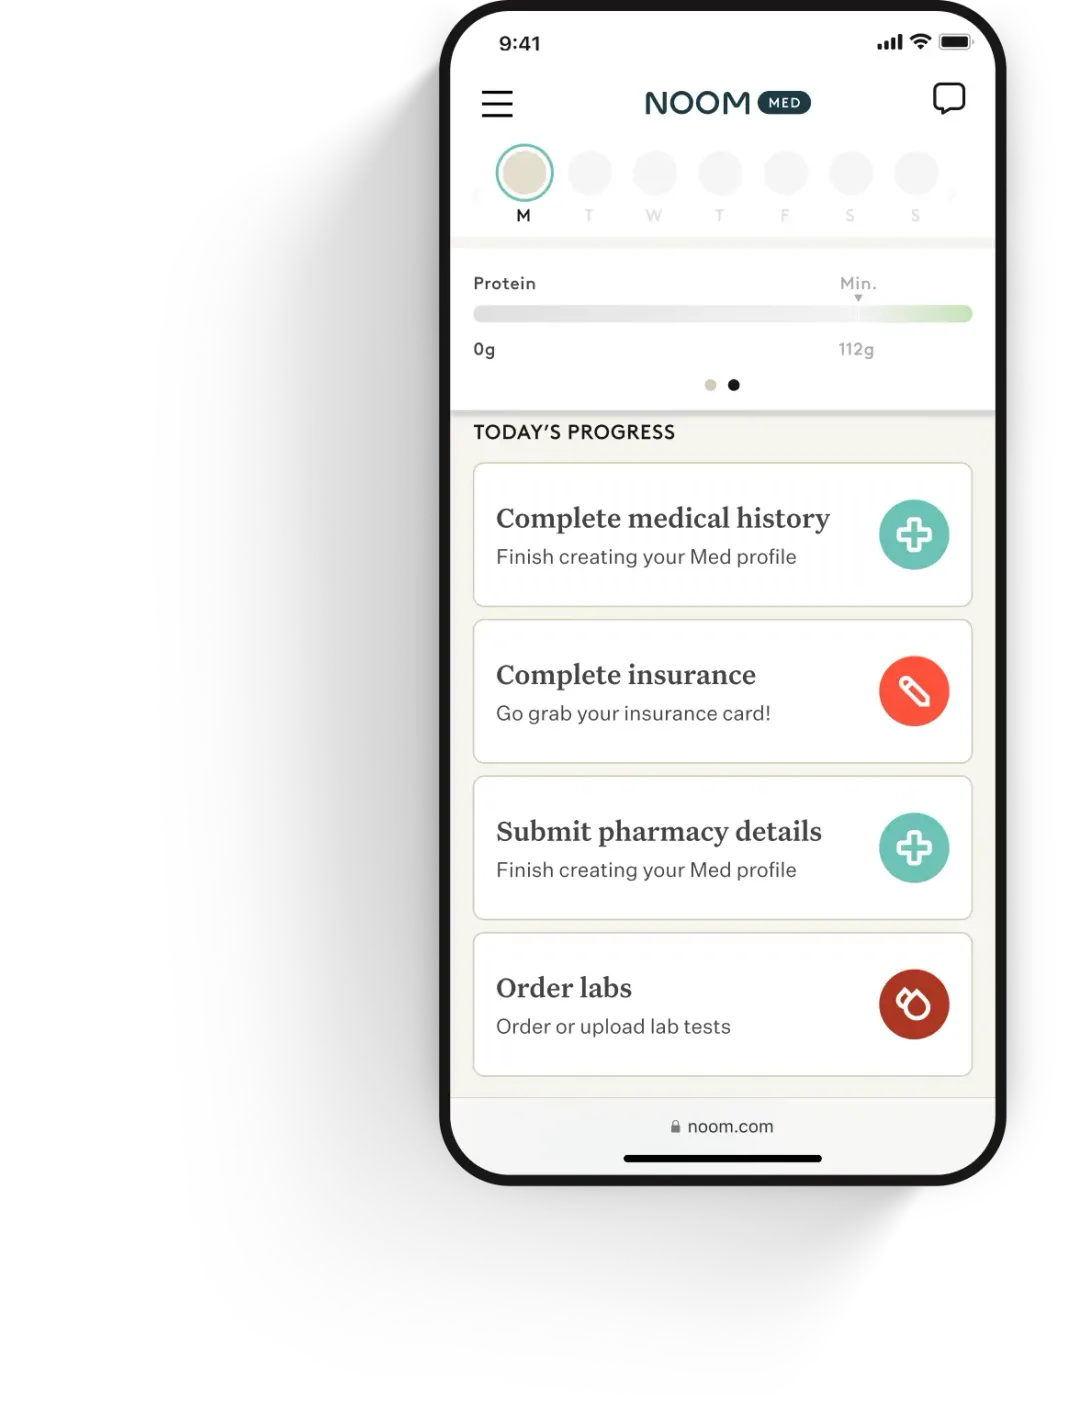

How to access Ozempic® with Noom

STEP 1

Complete a brief intake survey

Share your health history and weight-loss goals to get started.

STEP 2

Understand your health with labs

Take a quick and convenient metabolic lab test to get a picture of your health.

STEP 3

Consult with an expert clinician

A clinician will quickly evaluate your results and provide a prescription all online, if clinically appropriate.

STEP 4

Start losing weight with a customized medication and support program

If prescribed, you’ll get a custom plan designed for your goals and biology.

Ongoing care and medication

Stay on track with unlimited access to your clinician and medication refills, where clinically appropriate.